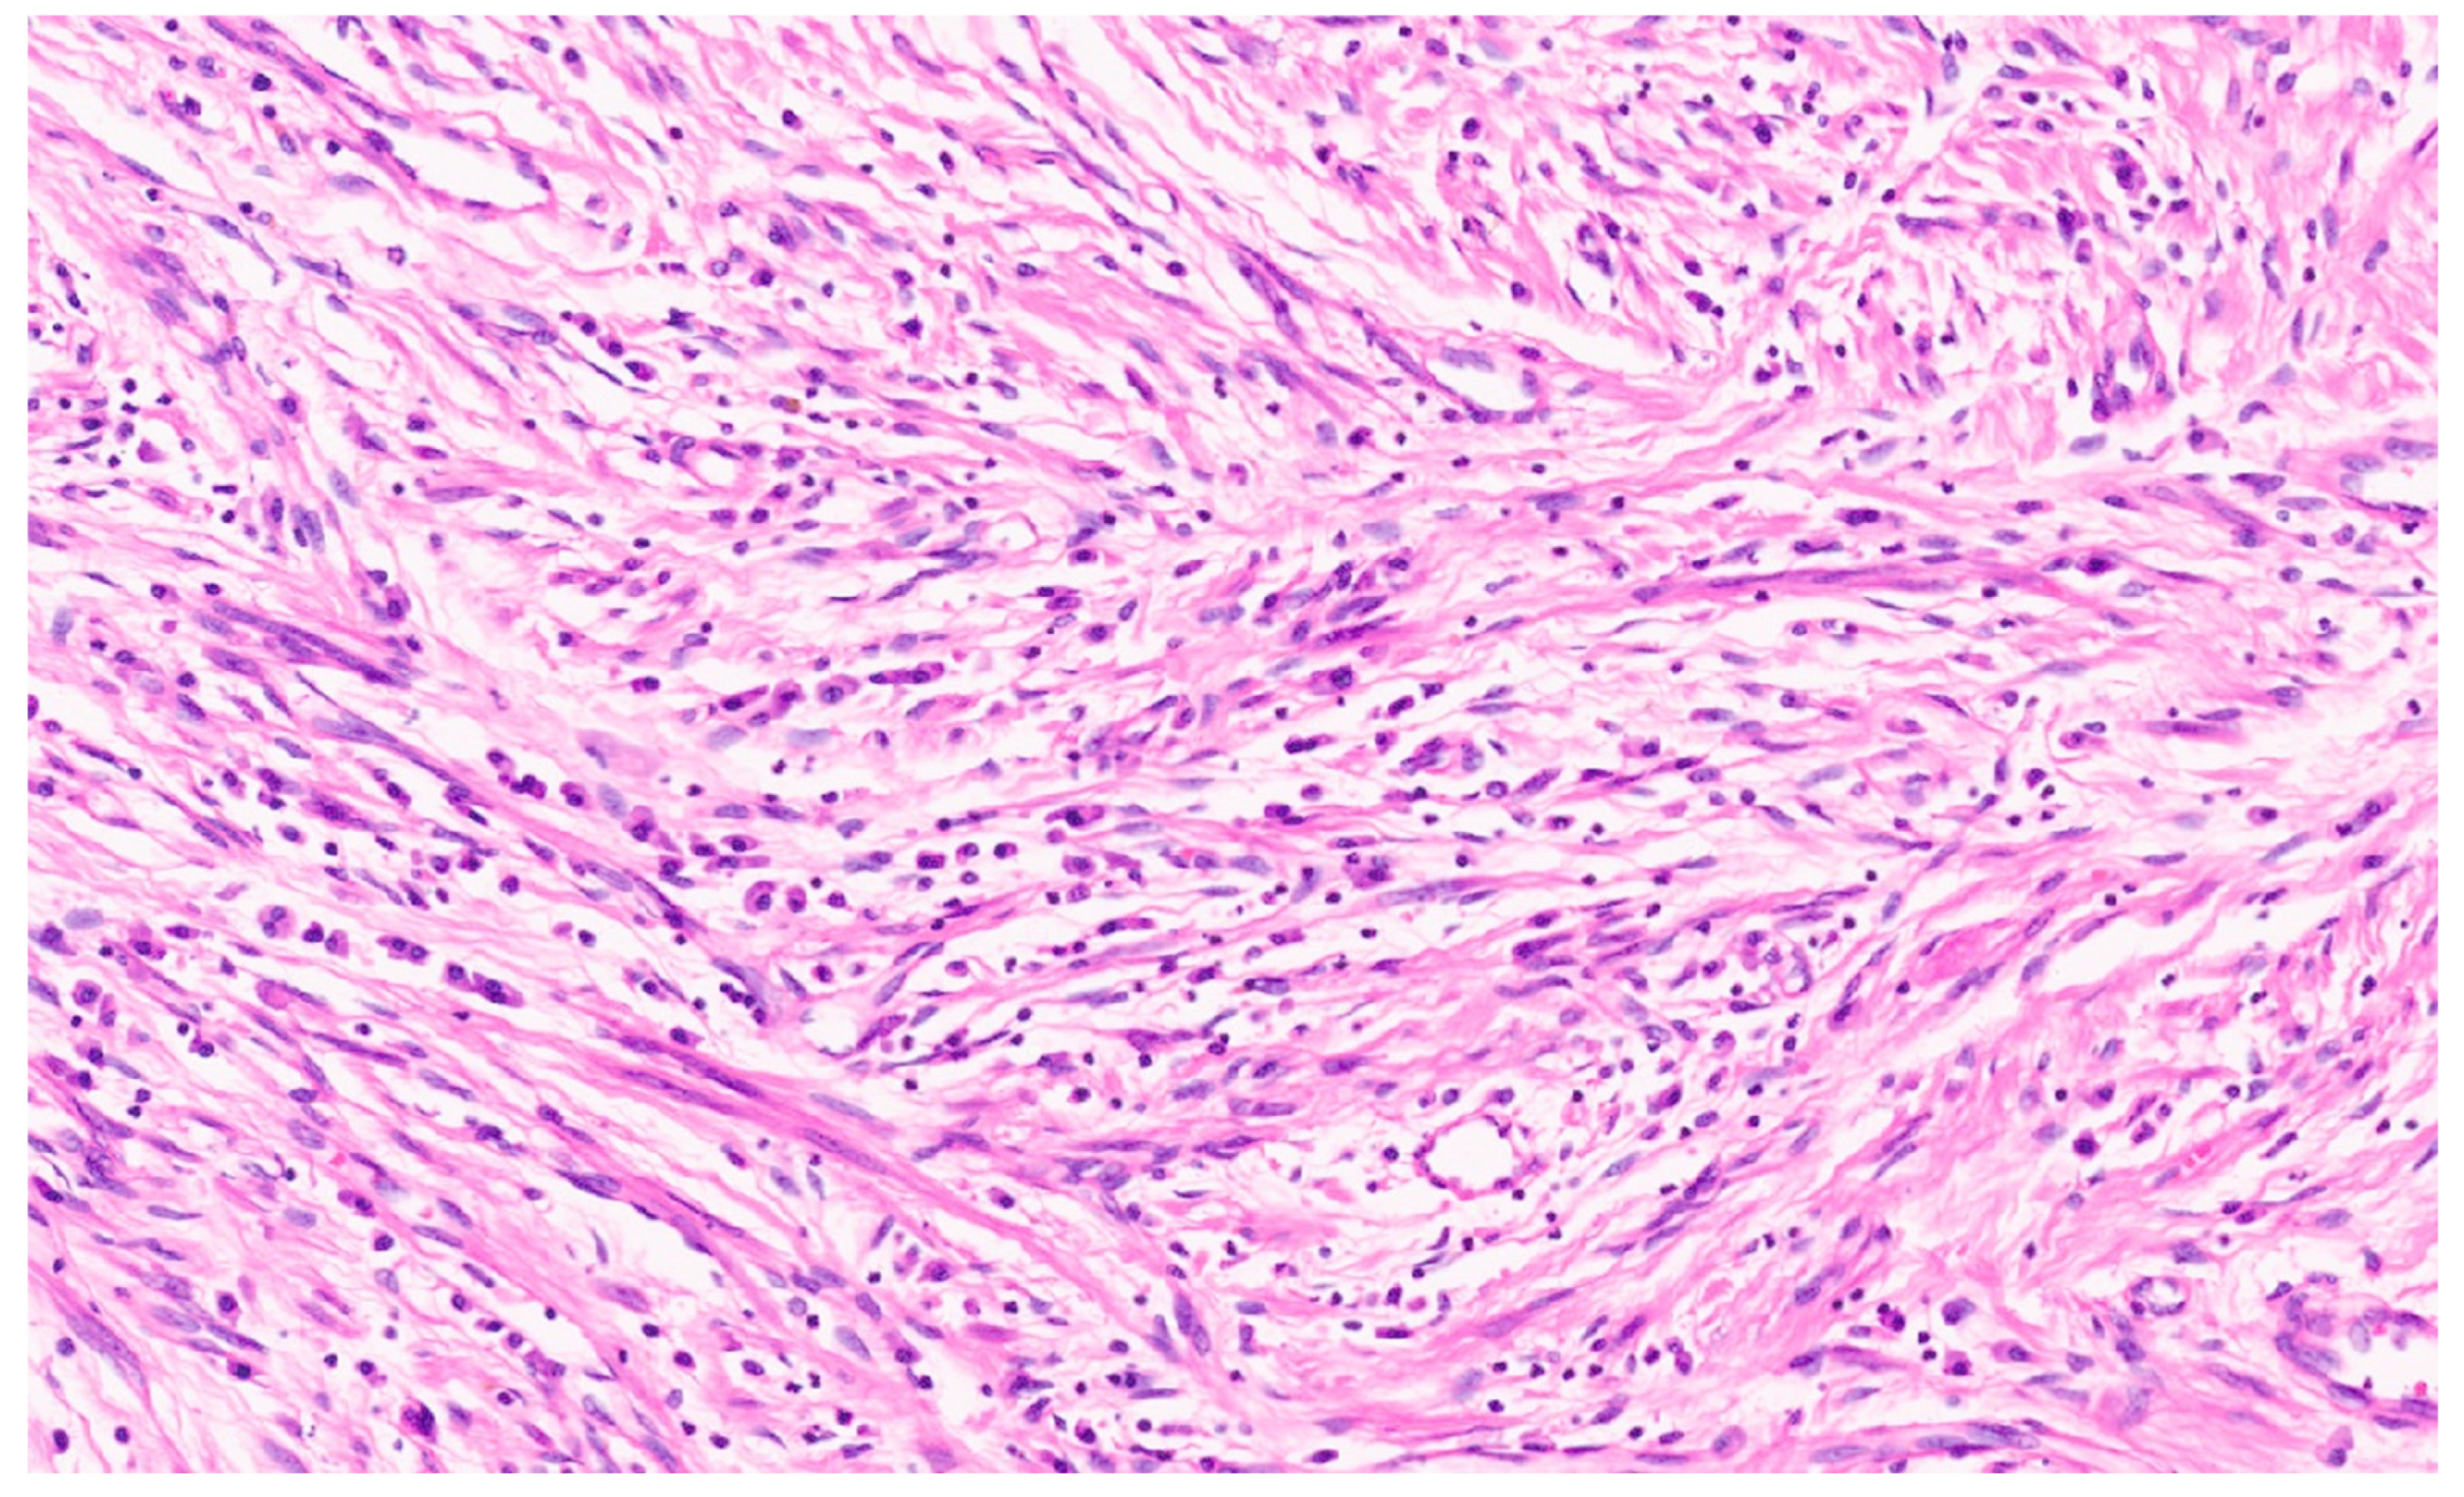

12.3. Pathology